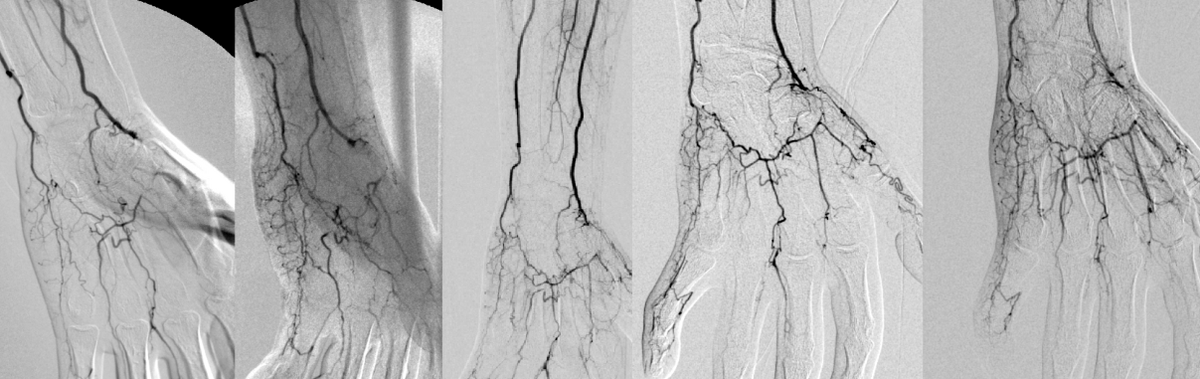

Sehr geehrte StudienteilnehmerinDie periphere arterielle Verschlusserkrankung („Schaufensterkrankheit“, pAVK) ist eine stenosierende (verengende) bis verschließende Erkrankung der Bauchschlagader und der Extremitätenarterien. Sie geht einher mit einer Durchblutungsstörung der betreffenden Extremität, z.B.: den Beinen. 5-10% der über 60-jährigen Bevölkerung leidet an einer symptomatischen pAVK. Häufigste Ursache der pAVK ist die Arteriosklerose.Als Risikofaktoren für die Entstehung arteriosklerotischer Gefäßkrankheiten gelten heute Hypertonie, Übergewicht, Fettstoffwechselstörungen, Diabetes mellitus, männliches Geschlecht, Alter, aber auch die Lebensweise, wie kalorien- und fettreiche Ernährung, Rauchen, Stress. Seit wenigen Jahren weiß man, dass die Veranlagung zur Arteriosklerose durch individuelle Erbanlagen bestimmt wird. Die Erbanlagen eines Menschen unterscheiden sich ganz natürlich in wenigen aber oft entscheidenden Punkten von denen eines anderen Menschen. Diese bestimmen u.a. die Entstehung und den Verlauf der Arteriosklerose und somit der peripheren arteriellen Verschlußerkrankung.Die Kenntnis dieser Unterschiede und ihrer Funktion in gesunden und erkrankten Menschen sind die Grundlage für den medizinischen Fortschritt. Dieser beeinflusst Krankheits-vorbeugende und therapeutische Möglichkeiten und damit eine verbesserte Lebensqualität des Menschen. Das ist Ziel unserer Abteilung.Zur Erstellung eines individuellen Risikoprofils ist es wichtig, den Einfluss genetischer Faktoren, Umweltfaktoren und den Lebensstil des Menschen zu berücksichtigen. Ziel des Registers: Erfassung von Risikofaktoren pAVK- erkrankter Patienten.Dabei sollen Modelle zur Identifizierung von Hoch-Risiko-Gruppen entwickelt werden, um die Basis für verbesserte Präventiv- bzw. Therapiestrategien zu schaffen. Unter anderem sollen Unterschiede in Genen, die an der Entstehung und dem Verlauf der Arteriosklerose beteiligt sind, bestimmt werden. Dabei wird zukünftig unter Berücksichtigung von Umweltfaktoren und Lebensstil das individuelle Risiko bestimmt, um Voraussagen für das Risiko einer Entstehung der Arteriosklerose machen zu können.Es ist zu erwarten, dass die erhobenen Daten wichtige Informationen über die den Komplikationen zu Grunde liegenden Mechanismen und zu den Verlauf beeinflussenden Risikofaktoren ergeben werden, die die Basis für eine gezieltere Therapie und Prophylaxe sind. Hieraus können langfristig Leitlinien zur Prävention sowie zur medikamentösen und interventionellen Therapie der pAVK-erkrankten Patienten entwickelt werden.Wir möchten Ihnen eine Blutprobe entnehmen: - 3 x 9 ml EDTA - 1x 10 ml Citrat - 2 x 9 ml Serum sowie einige persönliche krankheitsrelevante Daten erfassen. Es werden nur Gene und Laborwerte untersucht, die nach wissenschaftlichen Erkenntnissen wahrscheinlich eine besondere Bedeutung für die Entstehung und den Verlauf der Arteriosklerose haben. Ausserdem möchten wir Sie ausdrücklich auf die Möglichkeit hinweisen, dass zukünftig weitere, heute noch nicht benennbare genetische und laborchemische Untersuchungen hinzukommen könnten.Mit der Befragung bzw. Untersuchung sind keine zusätzlichen Gesundheitsrisiken verbunden. Die Blutproben werden bei -30 °C konserviert. Die entsprechenden Gefrierschränke im Uniklinikum Münster (Department für Kardiologie und Angiologie) sind gegen Zugriff durch Unbefugte gesichert. Herzlichen Dank für Ihr Interesse